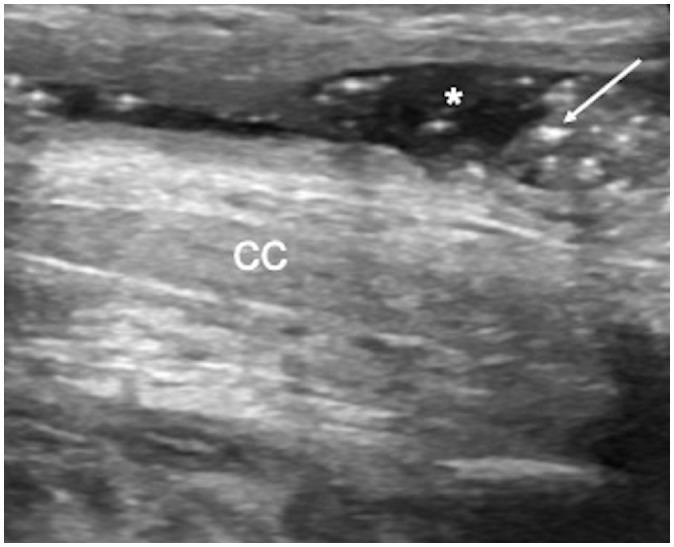

Penile emergencies are uncommon and can be categorized as having infectious, vascular, traumatic, or multifactorial etiologies. To facilitate early diagnosis and treatment during emergency, US and color Doppler imaging are imperative. US depicts hypoechoic collections regardless of the presence of air foci in infections like abscess and Fournier's gangrene. Color Doppler imaging is conducted to evaluate vascular conditions such as penile Mondor disease (PMD) and priapism. PMD is indicated by the absence of color flow and non-compressibility of dorsal penile vein. Priapism can be categorized based on cavernosal artery flow: high flow and low flow. In traumatic injuries like penile fracture, US reveals breach in tunica albuginea with hematoma. Peyronie's disease can be multifactorial in origin and the imaging is commonly visualized as thickening of the tunica albuginea and echogenic calcified plaques. Urethral injuries are urethral discontinuity with adjacent collection. Urethral calculus is visualized as echogenic focus with posterior acoustic shadowing. Therefore, effective collaboration between radiologists and urologists is required for appropriate initial diagnosis and prompt treatment.

阴茎急症并不常见,可分为感染性、血管性、创伤性或多因素病因。为便于在急诊时进行早期诊断和治疗,超声(US)和彩色多普勒成像必不可少。在诸如脓肿和福尼尔坏疽等感染中,无论是否存在气灶,超声均能显示低回声液性聚集。进行彩色多普勒成像以评估血管状况,如阴茎蒙多氏病(PMD)和阴茎异常勃起。阴茎蒙多氏病表现为阴茎背静脉无血流信号且不可压缩。阴茎异常勃起可根据海绵体动脉血流分为:高流量型和低流量型。在阴茎骨折等创伤性损伤中,超声显示白膜破裂并伴有血肿。佩罗尼氏病的病因可能是多因素的,影像学表现通常为白膜增厚和回声增强的钙化斑块。尿道损伤表现为尿道连续性中断并伴有相邻液性聚集。尿道结石表现为伴有后方声影的回声增强灶。因此,放射科医生和泌尿外科医生之间需要有效协作,以进行恰当的初步诊断和及时治疗。